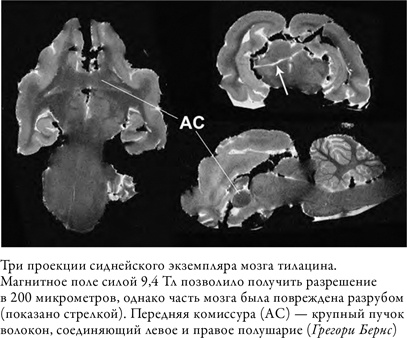

Наше терпение было вознаграждено уже хотя бы тем, что мы получили прекрасные структурные снимки мозга тилацина. Поскольку сиднейский экземпляр оказался в лучшем состоянии, чем смитсоновский, и поскольку мы сканировали в магнитном поле силой 9,4 Тл, разрешение вышло ошеломляющим. Видны были тракты белого вещества, которые мы не могли разглядеть в смитсоновском экземпляре. Однако разрез, который я заметил, когда мы закладывали образец в томограф, уходил гораздо глубже, чем ожидалось. Лезвие, которым он был сделан, рассекло мозг по диагонали от коры правого полушария до левого таламуса. Это означало, что проследить пучки белого вещества будет трудно, поскольку задеты оба полушария.